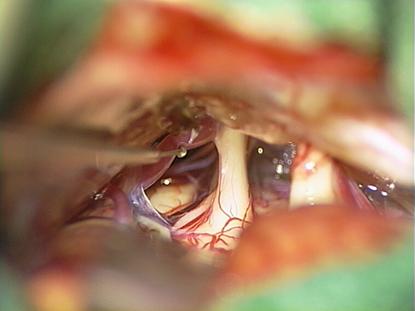

Mikrochirurgischer Einblick in die hintere Schbädelgrube zur mikrovaskulären Dekompression. Darstellung des Nervus trigeminus und der Gefäße in der hinteren Schädelgrube bei Trigeminusneuralgie

Deutlicher Kontakt zwischen

N. Trigeminus und einem Blutgefäß

(A. cerebelli superior)

Nach Lösen der arachnoidealen Haut stellt sich die neurovaskuläre Kompression am Nerven deutlich dar.